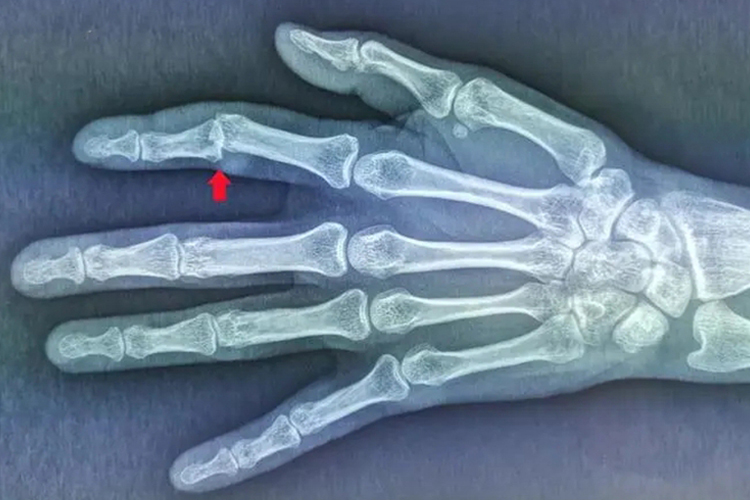

手指关节错位是一种常见的关节损伤类型,临床通常称之为关节脱位,包括半错位和完全性错位。它的发生和外伤、自身疾病等有关,通过正确的复位、适当制动、消肿等可以促进恢复。

- 外伤性:最常见的原因是受伤,如打篮球时手指被篮球戳到,导致指间关节脱位或指间关节韧带损伤,甚至骨折。

- 疼痛:由于错位导致周围韧带、关节囊和其他软组织损伤,产生明显的淤血和炎性水肿,神经组织也会受损,导致剧烈疼痛。

- 局部明显肿胀:错位导致周围小血管破裂、渗血,形成淤血堆积和炎性水肿,肿胀症状非常明显。

- 手指关节活动不利:错位后正常的手指关节屈伸功能无法实现,导致明显的活动受限。